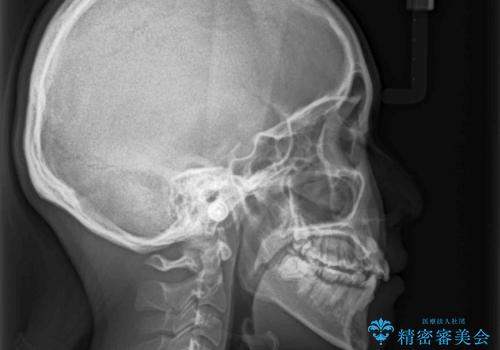

- 前歯のでこぼこと乳歯が残るほどの八重歯を気にして来院された患者様です。

非抜歯にてワイヤー矯正にて治療することとしました。(ただし、親知らずと乳歯は抜歯)

犬歯は歯根が太く長いため、移動には時間を要します。しかし、犬歯は機能面から考えて残すことを選択したいため、長期間をかけて治療を行うこととしました。